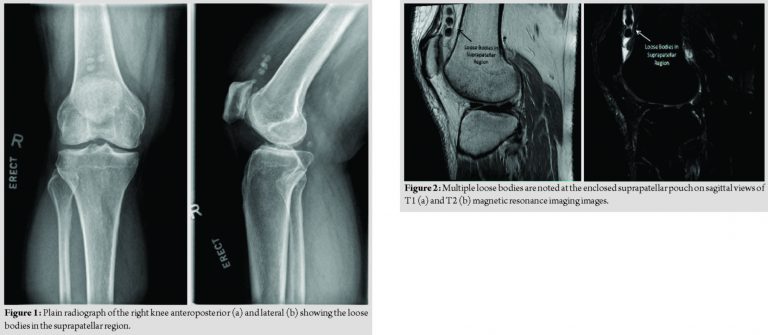

A 61-year-old man was referred to our tertiary center for atraumatic right knee pain lasting for 3 months. The pain was localized to the suprapatellar region and was worse with the knee in flexion. The knee pain was associated with occasional locking. On examination, mild quadriceps wasting was noted and moderate effusion was present. The medial and lateral joint lines were non-tender. The patient had a full knee range of motion of 0–120°. The patellar grind test was positive. The right knee radiographs revealed five loose bodies in the suprapatellar region, which were observed on sequential sets of radiographs performed 3 months apart. In addition, radiographic signs of osteoarthritic changes included narrowed medial joint space, mild osteophyte formation, and subchondral sclerosis (Fig.1). Differentials for the intra-articular loose bodies or calcification include synovial osteochondromatosis, chondrosarcoma, osteochondral fractures, and osteochondritis dissecans. Pre-operative magnetic resonance imaging (MRI) of the right knee revealed multiple loose bodies within the enclosed suprapatellar pouch with knee joint effusion (Fig. 2). There was a suprapatellar plica dividing the suprapatellar pouch into two cavities. There were foci of full-thickness cartilage wear in the medial tibiofemoral and patellofemoral joints, although the meniscus was intact. The patient underwent arthroscopic removal of the loose bodies in the suprapatellar pouch and debridement of suprapatellar plica.